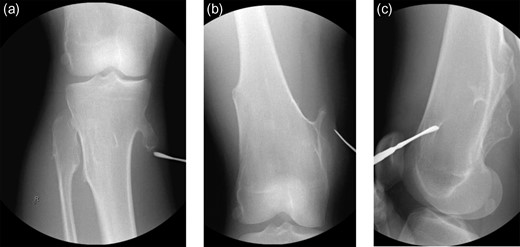

The patient is an 18-year-old female with history of MHE with many osteochondromas throughout her lower extremities who presented with acute right medial knee pain and inability to extend her knee, locked in a flexed position. The patient reports squatting in deep flexion when she felt a pop on the medial aspect of her right knee resulting in an acute inability to actively, passively or forcefully extend her knee past 90° of flexion. She has a remote history of fracture involving a right medial proximal tibial osteochondroma that has since healed uneventfully. On examination, there was tenderness localized to the medial hamstrings and soft tissues around her medial proximal tibial osteochondroma. Neurovascular function was intact. Forced knee extension could not overcome the locked knee joint and caused significant pain over the medial proximal tibia and along her hamstrings. Her patella–femoral joint was well-aligned, and she was non-tender over the anterior knee nor the medial/lateral joint lines. She had no knee effusion. Initial radiographs (Fig. 1a–c) confirmed multiple lower extremity osteochondromas, notably with a large, pedunculated osteochondroma at her right medial proximal tibia, well-healed since her previous fracture. No advanced imaging studies were performed as clinical concern for intra-articular pathology was low and patient positioning prohibited. Assessment was a locked knee secondary to incarcerated hamstring tendons around her longstanding right medial proximal tibial osteochondroma. Operative intervention was planned for excision of the osteochondroma and exploration of the soft tissues.

(a–c) Presenting radiographic images with knee locked in flexion.